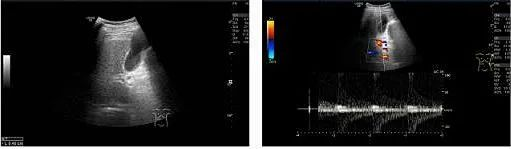

2023-07-25肝胆胰脾彩色多普勒:肝硬化,肝门静脉纤细,血流反向,门静脉高压可能。胆囊壁稍粗增厚。脾稍大。腹腔未见明显液性暗区。

1)超声复查

TIPS术后:

? 支架内血流充填好,支架内峰值流速206cm/s

? 门静脉主干内径12mm,门静脉血流信号充填良好,为单色向肝血流,PSV 72cm/s

? 脾静脉胰腺段内径9mm,PSV 37cm/s,脾门处内径10mm,PSV 36cm/s

? 肠系膜上静脉近汇合处内径9mm,PSV 41cm/s